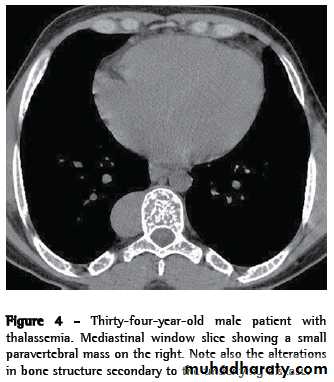

THALASSEMIA (COOLEY'S ANEMIA)

Genetic disorder characterized by diminished synthesis of one of the globin chains.Radiographic features

Hyperplasia of marrow is the dominant feature.* Expands the marrow space: hair-on-end skull

* Modeling deformities of bone: Erlenmeyer flask deformity

* Premature closure of growth plates

* Paravertebral masses due to extramedullary hematopoiesis

Vascular occlusion